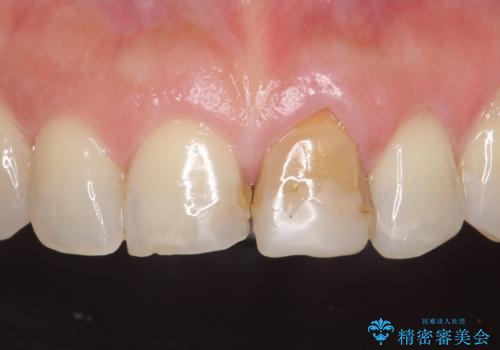

- 前歯の変色が気になるのでセラミックによる治療を行いたいといらっしゃった方の症例です。

左上1番目の歯の再根管治療終了後、左右1番目の2歯をオールセラミッククラウンで補綴しました。